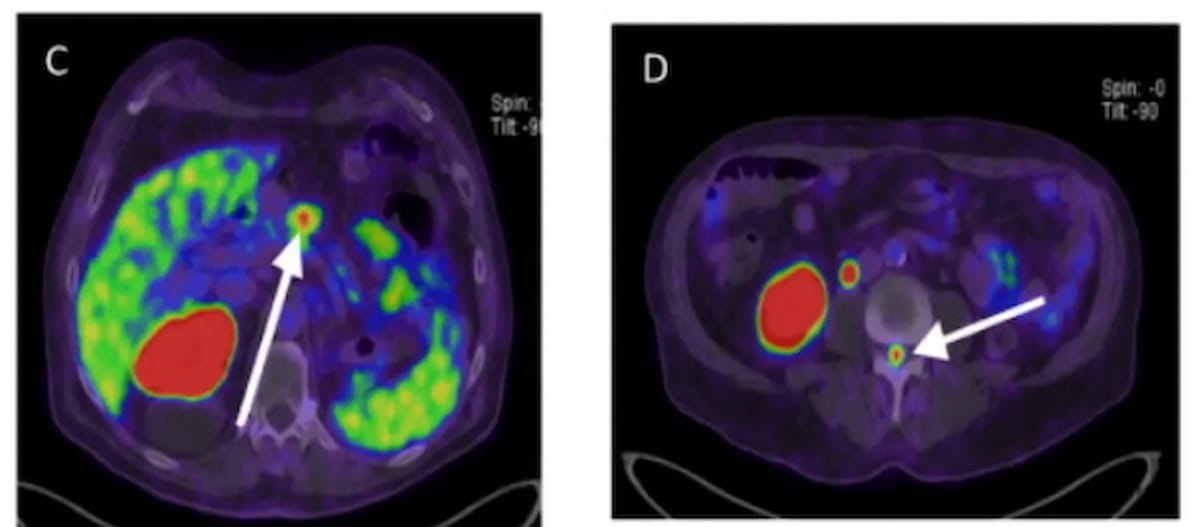

Sixty-five percent of patients with newly diagnosed high-risk prostate cancer may have extraprostatic extension on MRI, and PSMA PET/CT findings suggest those with Gleason scores of eight or higher have more than double the risk of metastasis, according to a new study presented at the European Congress of Radiology (ECR).